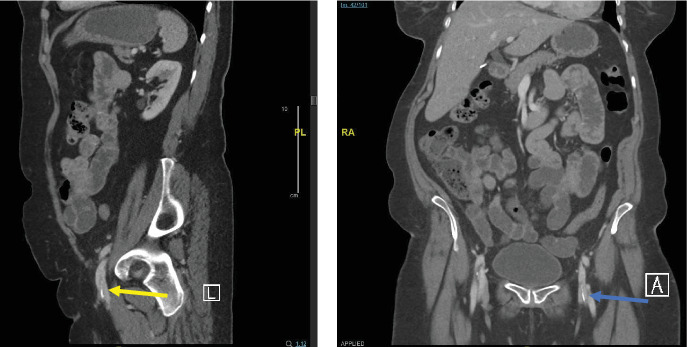

Introduction: Phlebolith is a term that refers to round-shaped calcified thrombi commonly located in the pelvic region. The occurrence of dense, linear calcifications or phlebolith-like formations within the soft tissues of the lower extremities, particularly in the superficial femoral, greater saphenous, or popliteal veins, is rare. Patient Concerns: This study presents the case of a 73-year-old woman who was being evaluated for postmenopausal bleeding. During the patient's diagnostic workup, an incidental linear-shaped phlebolith was discovered. She had a positive history of deep vein thrombosis (DVT) for 36 years following her previous vaginal delivery. Diagnosis: Upon further examination and imaging, the patient was found to have a chronic calcified thrombus in the iliofemoral, popliteal, great saphenous, and superficial femoral veins, which was initially reported as a foreign body in the femoral vein on computed tomography (CT). Interventions and Outcomes: Conservative management was undertaken, with no worsening of her condition upon further follow-up. Conclusion: This study showcased a rare form of a radiographically visible calcified thrombus in the veins of the lower extremities of our patient. Calcified venous thrombosis in the lower extremities is rare, as previously documented cases of venous calcifications have been observed in the pelvis with round shapes or as phleboliths. The common presentations differ from those in our case, making it important to consider such cases when formulating a differential diagnosis. While the precise mechanisms behind the formation of calcified thrombi remain unclear, this study emphasizes the significance of further exploration and future case studies to shed light on this enigmatic phenomenon.

导言:静脉结石是一个术语,指的是通常位于骨盆区域的圆形钙化血栓。在下肢软组织,特别是在股浅静脉、大隐静脉或腘静脉中,发生致密的线状钙化或静脉样形成是罕见的。患者关注:本研究提出了一个73岁的妇女谁是评估绝经后出血的情况。在病人的诊断检查中,偶然发现了线状静脉结石。她有深静脉血栓(DVT)阳性病史36年后,她的阴道分娩。诊断:经进一步检查和影像学检查,发现患者在髂股静脉、腘静脉、大隐静脉和股浅静脉有慢性钙化血栓,最初在CT上报告为股静脉异物。干预措施和结果:采取保守治疗,进一步随访时病情未恶化。结论:本研究显示了一个罕见的形式的钙化血栓在我们的病人的下肢静脉放射可见。下肢静脉钙化血栓是罕见的,因为以前有文献记载的静脉钙化病例在圆形骨盆或静脉结石中被观察到。常见的表现与我们的病例不同,因此在制定鉴别诊断时考虑这些病例很重要。虽然钙化血栓形成的确切机制尚不清楚,但本研究强调了进一步探索和未来案例研究的重要性,以阐明这一神秘现象。